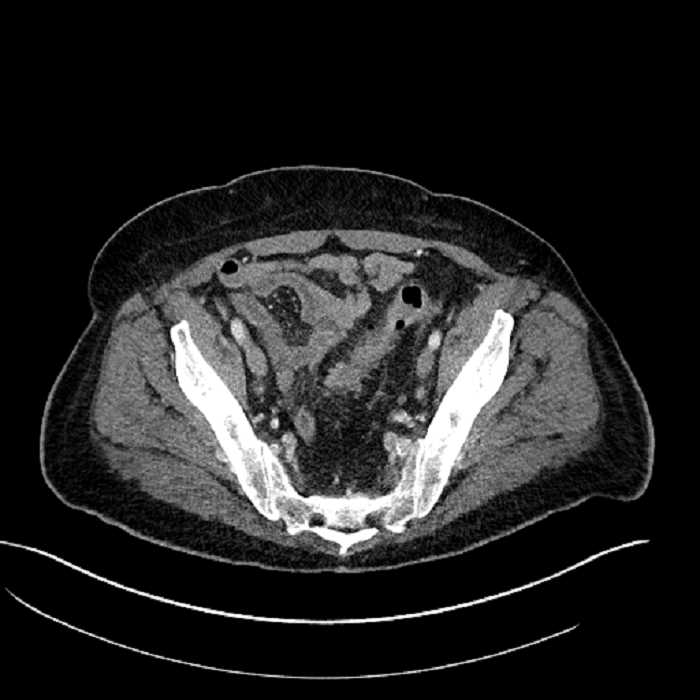

• High grade stenosis of the left common iliac artery, with the left internal and external iliac arteries remaining patent

High grade stenosis of the left common iliac artery. The left external and internal iliac arteries are patent.

Hepatic abscess showing the double target sign with low density internally surrounded by a thin inner enhancing rim (red arrow) and ill-defined outer low density rim (yellow arrow). Blue arrow indicates an internal septation. Red arrows: additional smaller subcapsular abscesses. Red arrow: focal contained perforation associated with diverticulitis.